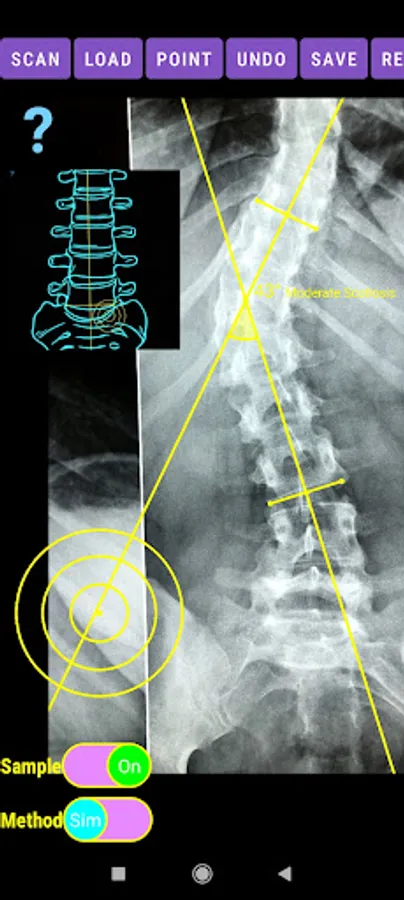

The app offers a very convenient way to asses spinal deformity by measuring the Cobb angle. The first thing is to load one image from your photo library or capture a photo from x-rays photos of a patient. The app offers two measuring methods, the simple (Sim.) and the extended (Ext.). By clicking the relevant option, the option is highlighted and the respective method is activated.

-Offers a very convenient way to determine the most accurate possibly way at once. By marking four points at the same X-ray, at each spine the App calculates the Cobb angle. In cases where values are out of normal ranges, the scoliosis is categorized according to measured angle as mild, moderate, severe. To simplify the process and to minimize inter-observer errors usually by not selecting the actual end vertebra, the app offers also in ext mode the ability to draw the vertical reference line through the patient’s sacrum and to identify more easily the end vertebrae (ext method).